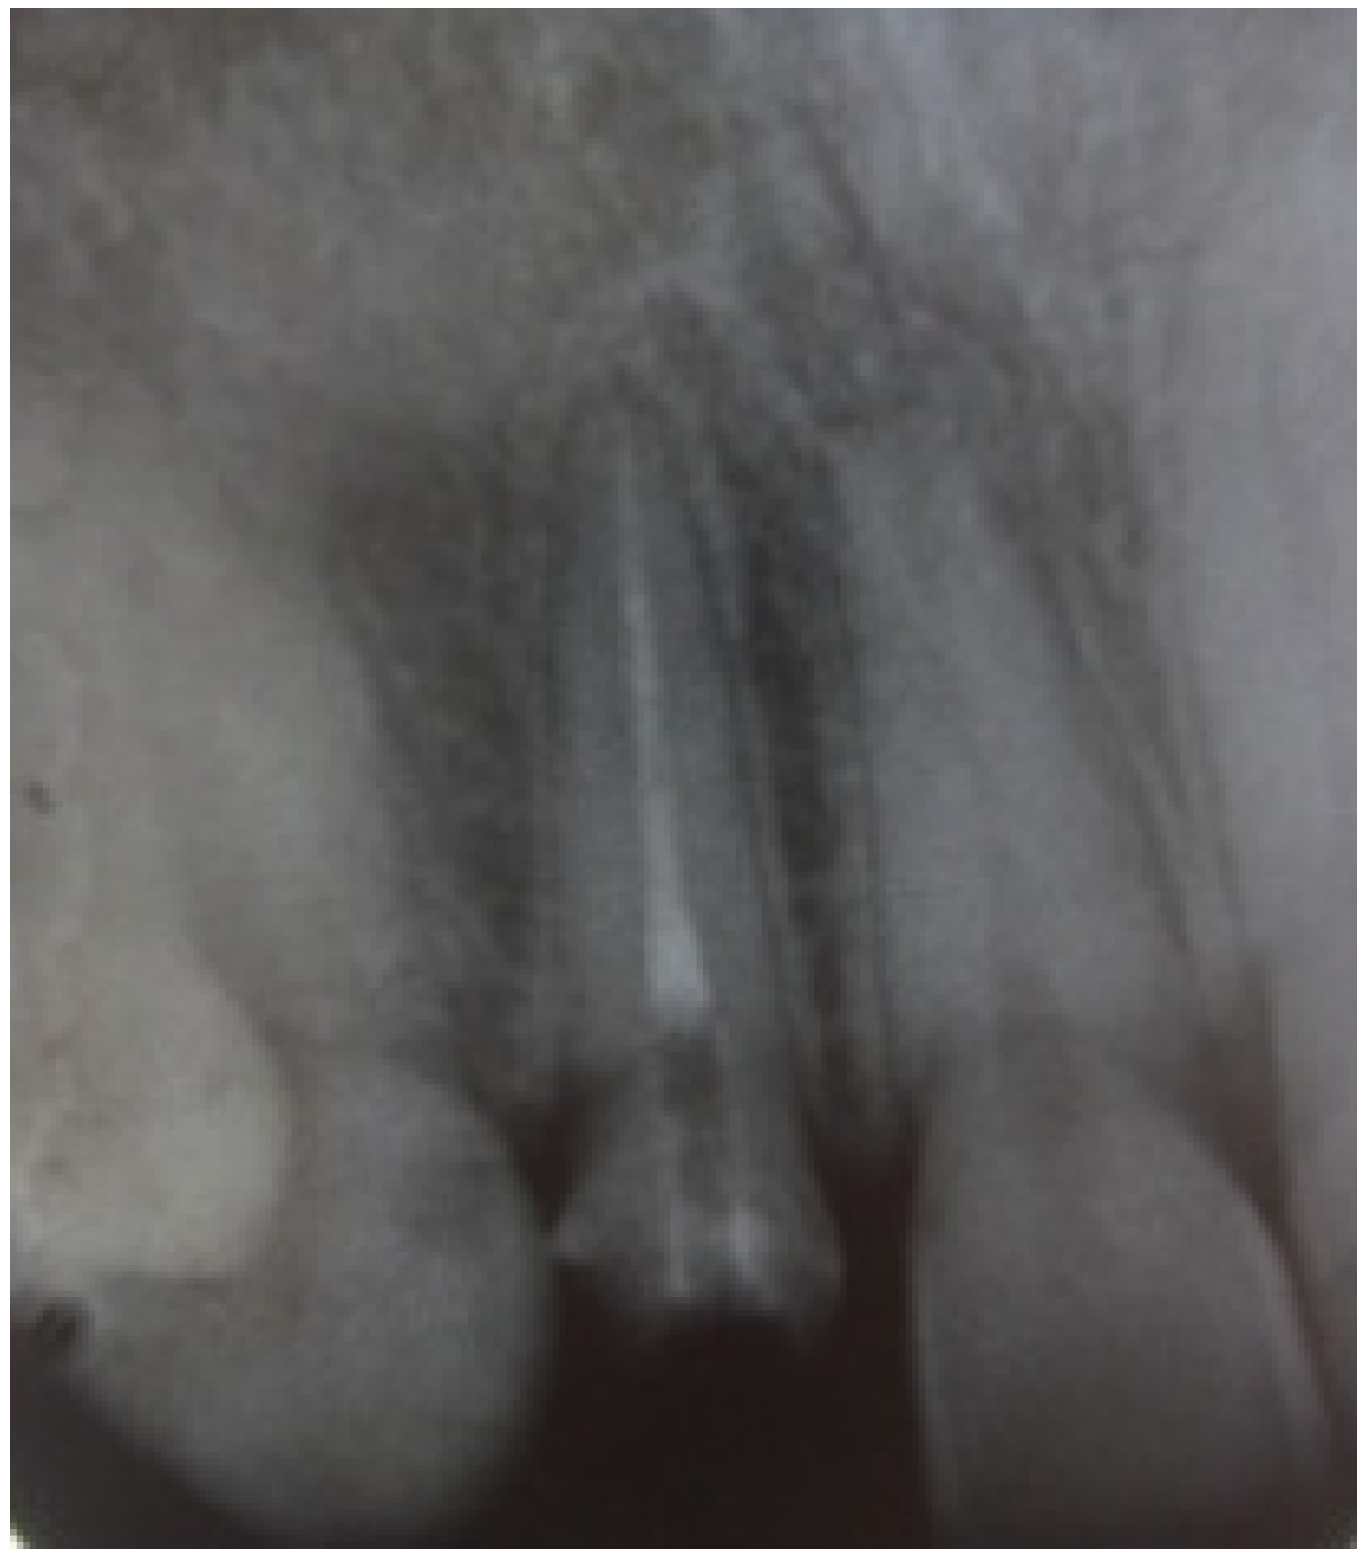

Gingival display was evaluated as more than 4 mm on the side of the lateral incisor when smiling. Radiographic examination revealed an adequate root canal filing with no bone loss.

The margin level of the lateral incisor was planned to be 1 mm coronal to the central incisor. The waxed cast served as a guide for provisional restoration which had been optimized after the periodontal therapy until the objectives desired in the final restoration were achieved. The old crown was removed and the remaining tooth structure was evaluated as sound. Radiological reevaluation showed an adequate distance between the bone crest and the residual dental tissue (>3 mm) including biological width (Figure 3).

Figure 3. Radiological reevaluation showing the distance between crestal bone and inter proximal preparation level.